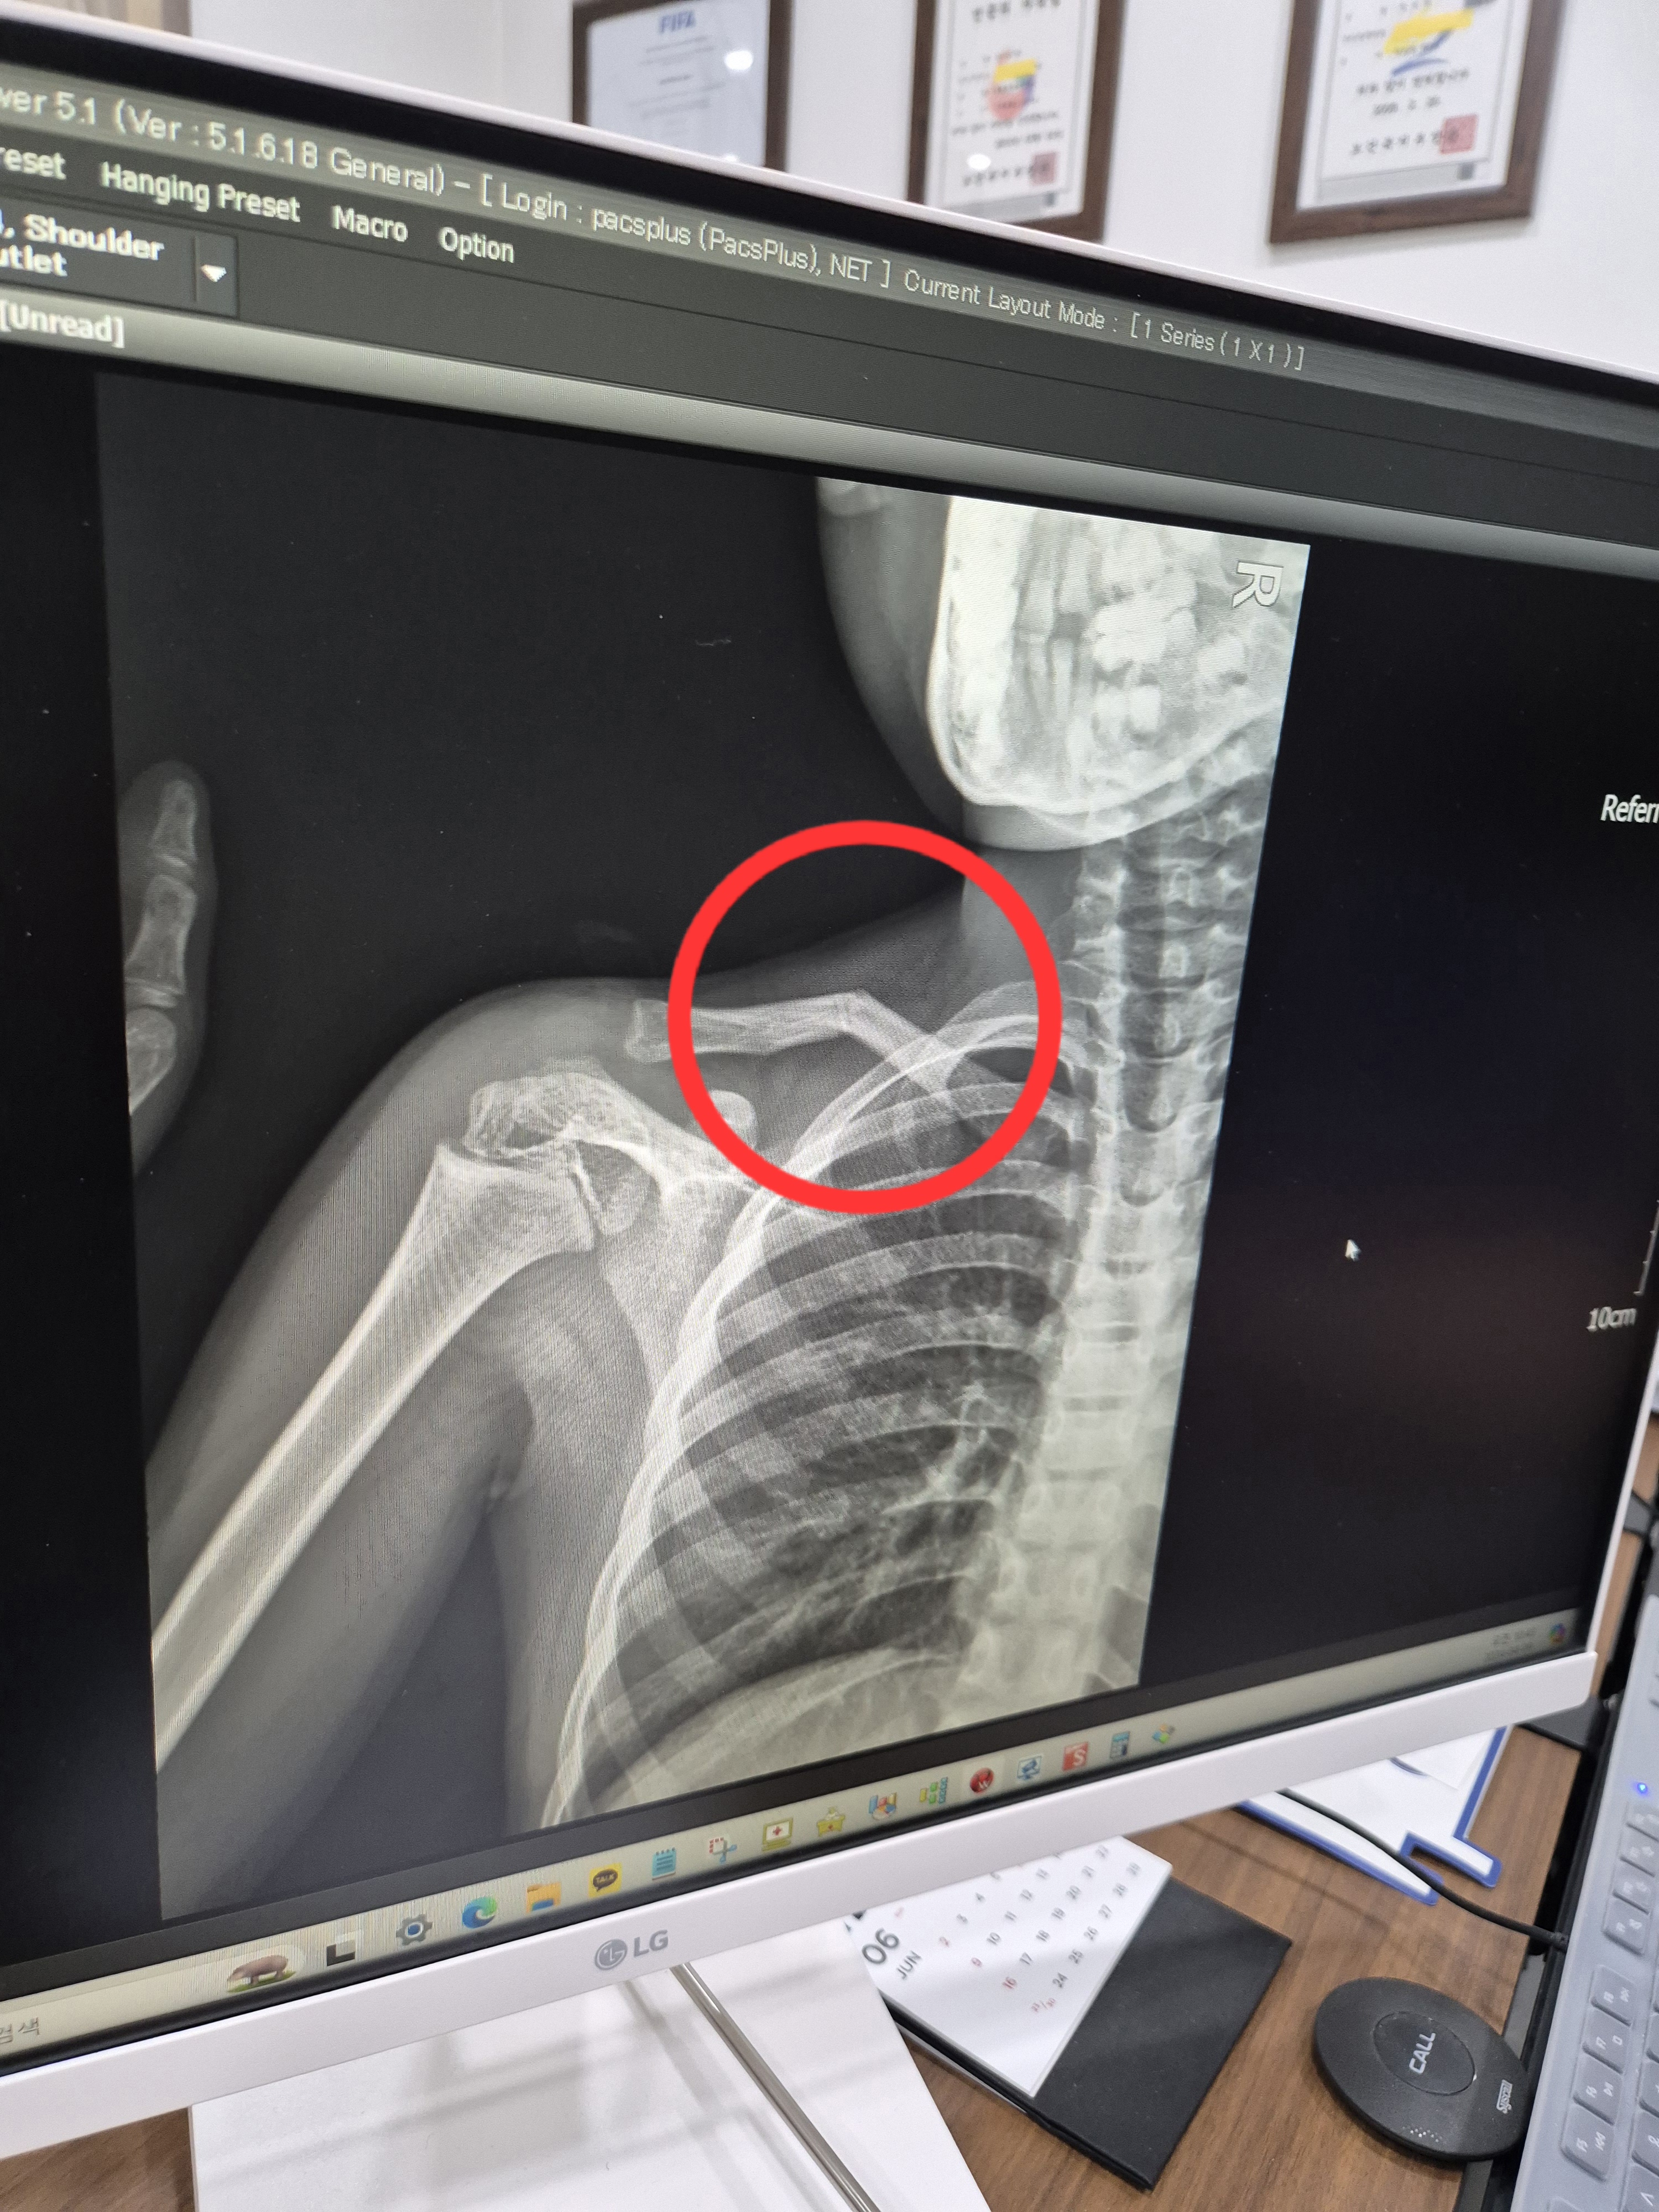

왼쪽이 부러진 쇄골 오른쪽이 정상 쇄골의 뼈모양이에요.

사진보면 완전히 어긋나있는데 부러졌을때 아이가 얼마나 아팠을까요ㅜㅜ

쇄골 부러지고 두달 지난 사진이에요.

부러진날 보면 뼈가 심하게 어긋나 있었는데 많이 내려온게 보이시죠? 저게 다 붙은거래요~